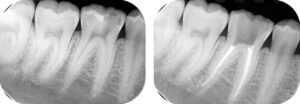

Nas imagens a seguir apresentamos casos: à esquerda, o dente com infecção. À direita, após o tratamento de canal, o dente tratado e preservado (imagem radiopacas mais claras/brancas dentro dos condutos dos canais).